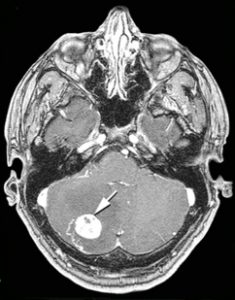

Projet de recherche sur les hémangioblastomes

Point de Caroline PIROU – Institut Gustave Roussy à Villejuif lors de L’AG VHL France du 19.02.2019 L’hémangioblastome (HB) est une tumeur méconnue, dont l’élucidation des origines et des mécanismes nous échappe encore puisqu’il n’existe pas de modèle animal de la maladie…

Projet de recherches sur les hémangioblastomes à l’Institut Gustave Roussy (IGR)

Voici une vidéo de présentation du projet de recherches initié en 2016 par le laboratoire de recherche du Professeur Stéphane Richard de l’IGR